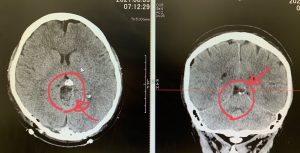

以下の写真の通り、脳の最深部に発生している良性腫瘍Falcotentorial meningioma に対し、

開頭での顕微鏡下手術による摘出術を実施し良好に摘出できています。

手術中はSEP神経モニタリングを実施しながら行うことで術後合併症なく安全に手術ができるよう細心の注意を払っています。